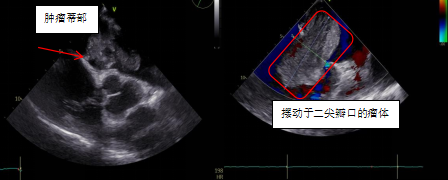

患者鄭大爺,因“反復勞累性心累、氣促2+月,加重10+天”到我院胸心血管外科就診。本次病情發作后,鄭大爺夜間無法平臥,呈端坐呼吸,伴咳嗽、咳痰,為白色泡沫痰,心悸、心慌明顯,并感頭暈,測血壓偏低,為休克狀態(80-90/40-50mmHg)。入院經心臟彩超、胸部影像學等相關檢查,發現導致鄭大爺癥狀的元兇:“巨大左心房占位”,支持粘液瘤樣改變,同期發現患者伴有卵圓孔未閉、三尖瓣中度關閉不全等心臟問題。

圖片

患者心臟彩超結果